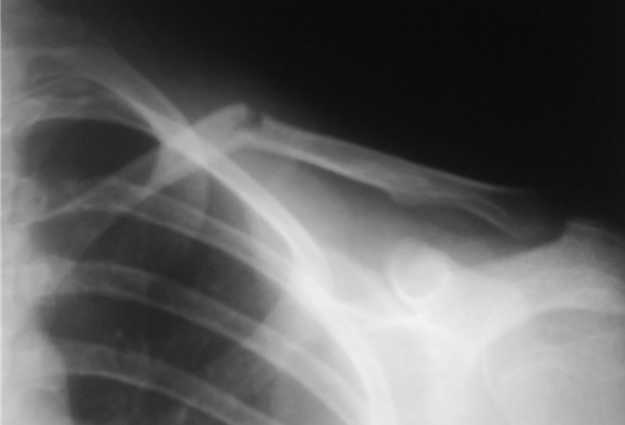

Перелом ключицы

Уважаемые коллеги, травматологи, памятуя о недавней дискуссии о лечении диафизарных переломов ключицы, "Как ключицу не лечи, все равно правильно срастется", поведаю о таком случае.

Девочка 14 лет, на даче упала с турника 05-07-08, в наш травмпункт обратились на следующий день - Диагноз: Закрытый перлом диафиза левой ключицы. Дежурным травматологом наложена 8-образная гипсовая повязка. На следующий день, родители привели девочку с жалобами на давление в левом надплечье и онемение правого предплечья и 1,2, 3-го пальцев кисти.

Мной была немедленно снята наложенная накануне повязка, и заменена на марлевую Дезо. 09-07-го, Дезо заменена на "косыночную" повязку.Сегодня произведен контрольный снимок -На сегодняшний день сохраняется онемение 1-3 пальцев.